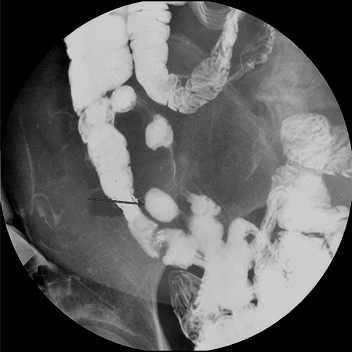

| Image TDM en coupe axiale du

diverticule multiple du grele . Image hydroaerique

des diverticule le long de l'intestin (fleche rouge

) . La paroi du diverticule est tres mince , en

differentiel avec la paroi de l'intestin ou du

colon, sa paroi est plus epaissisement que la

diverticule . |

Diverticule de

l'intestin : Aspect radiologique TDM en coupe axiale

. Image hydroaerique avec sa paroi tres mince .. |